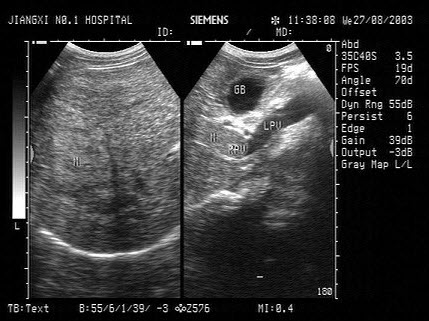

根据以下肝超声检查声像图,诊断为()

A.肝癌并门脉癌栓

B.肝硬化

C.脂肪肝

D.肝炎

E.血吸虫性肝硬化并门脉血栓